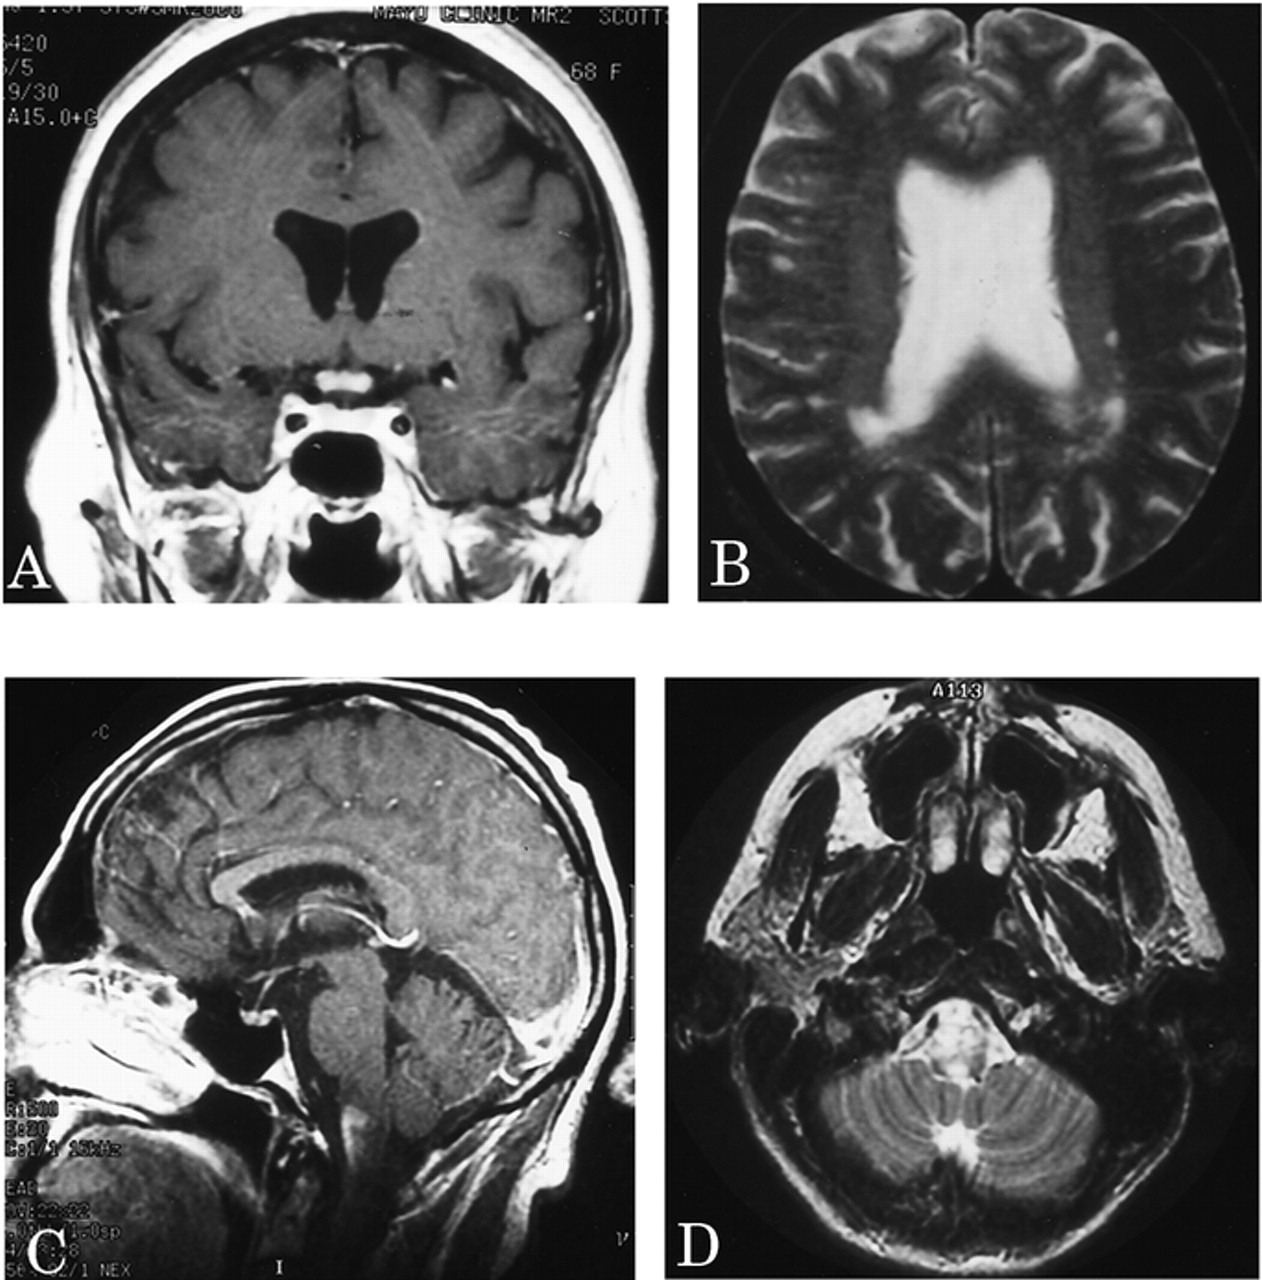

特征典型的或明显的动了图4。脑部核磁共振进行了28 patients-27复发和1单相。中间间隔从第一个索引事件最初的大脑核磁共振是7.5个月(范围0.5 - 194)。视神经增强被认为在5 6例(83%)在2周内学习的一集。大脑实质是正常的在22个28初始扫描(79%);只有3 28(11%)满意的标准徽章等。10女士三个病人增加了T2信号在相邻的髓质纵向广泛的上颈椎脊髓损伤(见图4中,C和D)。

图4。选择先生大脑的图像。(A)扩散增强视神经交叉的gadolinium-enhanced t1日冕图像。(B)几室周的病变中看到一个病人在t2加权图像轴。(C和D)损伤扩展的吻侧颈绳在髓质gadolinium-enhanced t1矢状轴向和t2加权图像。

十六个复发患者多个大脑核磁共振;最初的扫描是正常14。后续核磁共振成像显示,7仍然正常(第一个和最后一个MRI的平均时间间隔,11个月;范围1 - 39)6开发了非特异性异常,不符合标准的徽章等。10女士(平均间隔23个月,范围3 - 85),和1个病人“转换”来满足女士标准103个月后。